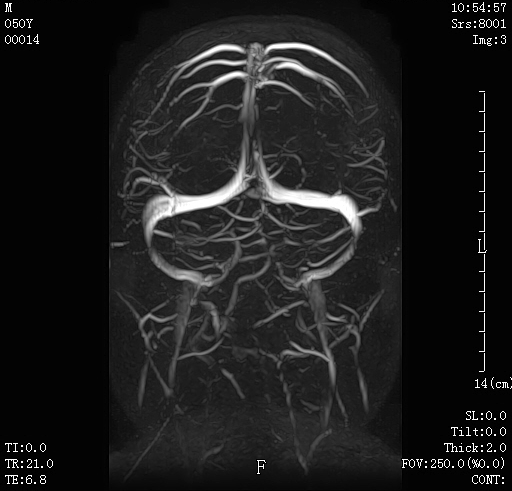

09 颈部血管成像,清晰显示颈部血管。

10 脑血管清晰显示